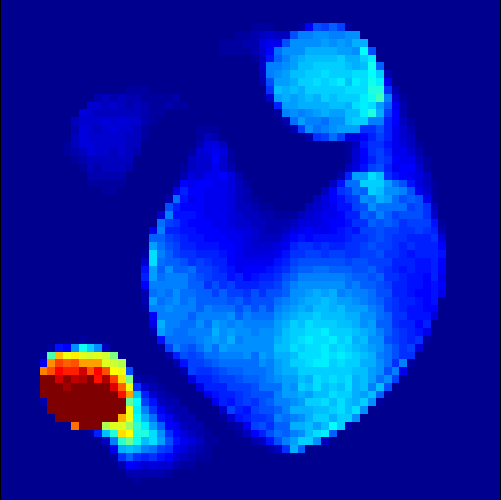

The first data set consists of a heart-shaped region and three circles on a static background (see figure 1 (a)). The two smaller circles are assumed to belong to

the same tissue type and therefore to the same subregion, which causes a total of four subregions, including the background. To simulate a more realistic application of dynamic SPECT

imaging, we used a synthesized representation of a rat liver as a second data set (see figure 1 (b)). The temporal concentration curves used to simulate the data sets

are shown in figure 2. As before, the total number of subregions was chosen to be equal to four in order to provide a both simple and realistic shape model.

In a first test, every image sequence was reconstructed out of the exact given sinograms. Additionally we tested noise corrupted data by first scaling the sinogram by a parameter , corrupting them with Poisson noise via the MATLAB imaging toolbox command imnoise and finally rescaling the image to the original range (see figure 4). The average count number per time step (i.e. the average of the discrete -norm of the data at each time step) is approximately in case of the heart-shaped data set and ca. in case of the rat liver simulation. The results at a certain number of time steps can be seen in figure 6 and 7. For comparison, we additionally performed a reconstruction with a simple alternating EM method, keeping the assumption that the tracer can be modelled as a sum of indicator functions and subconcentration curves, but neglecting any regularization terms. In all tests, the outer iteration number was set to 1000 with 10000 inner iterations per subproblem, to obtain a result within a reasonable time period. As stopping criterion, we chose the primal dual residual (cp. [12]) for the inner and the maximum over the Frobenius norms of and for the outer iterations. The results are displayed in 6 and 7 respectively.

As one can see in both figures, the reconstruction method applied to each data set performs very well, especially in contrast to the simple alternating EM method. This clearly shows the benefits of the proposed regularization methods. In case of noise-free given data, the shape of every object, where especially the heart is of higher interest, is clearly defined. As expected, we often observe errors in the edges of each region and where two regions are directly connected (the heart and the upper left circle). This causes the algorithm to incorrectly assign these pixels to another region. Furthermore, the reconstruction difficulties increase with an increase in noise. Some more pixels are assigned to the wrong region, which leads to a small hole-like structure within the heart region and causes a slight blurring effect. In the second data set the method clearly outperforms several other approaches by providing very clearly defined regions and even reconstructing fine structures of the phantom. However, as mentioned before, a clear reconstruction of the rat liver required highly optimized parameter sets, which makes the whole problem quite susceptible to parameter changes.